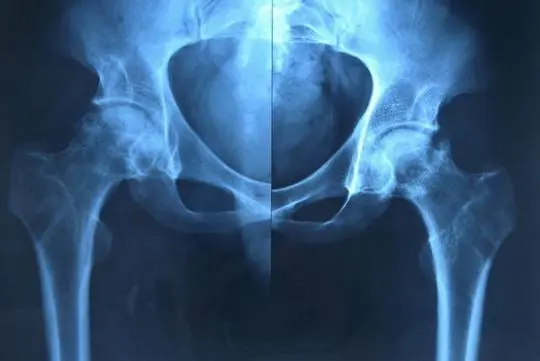

到后期随着股骨头变扁就是塌陷,或者疼痛会加重,也会出现走路的跛行,这个时候的影响比较大,下肢的左髋关节外展、外旋受限,就是膝盖往外撇,外展、外旋受限,或者外展、外旋疼痛加重,这种是最明显的。但是随着后期病变再进一步加重了,走路的跛行会越来越重,疼痛的时间也会越来越长,不再分是在剧烈活动或不活动,甚至夜里睡觉的时候也会有静息的疼痛,同时还有髋关节不仅仅是外展、外旋受限,往前伸、往后伸、前屈、后屈、内旋都会有相应的受限表现。

通过了解股骨头坏死的具体表现,就可以反过来协助自己针对股骨头坏死诊断,股骨头坏死的表现包括两点,首先就是疼痛,其次就是功能障碍,行走时会跛行,因为行走的时候引起疼痛,所以就会造成疼痛性的跛行。疼痛症状一般是局限在髋关节部位,不会向患侧的下肢往下放射,需和椎间盘突出进行明显的鉴别。